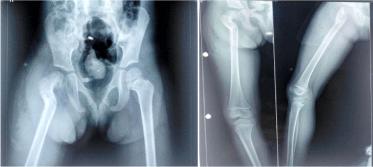

A Case of Intertrochanteric Valgus Osteotomy for Delayed Presentation of the Paediatric Post-Traumatic Coxa Vara After Neck of Femur Fracture

Dr. Alok Chandra Agrawal 1 Dr. Punit Gaurav* 2 Dr. Harshal S. Sakale 3

Background: Coxa vara in children is a rare but functionally disabling complication following femoral neck fractures, often arising from malunion or growth disturbances. Correction requires addressing both mechanical alignment and physeal orientation to prevent recurrence. This report highlights a successful intertrochanteric valgus osteotomy using a proximal femoral locking plate in a young child with post-traumatic coxa vara.

Case Presentation: A…